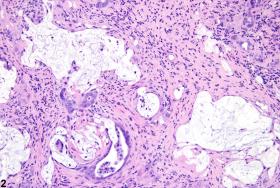

Full Text: http://tpx.sagepub.com/content/38/7_suppl/5S.full  - Cholangiofibrosis-arrows indicate incompletely lined proliferating bile ducts in a female Harlan Sprague-Dawley rat in a chronic study.